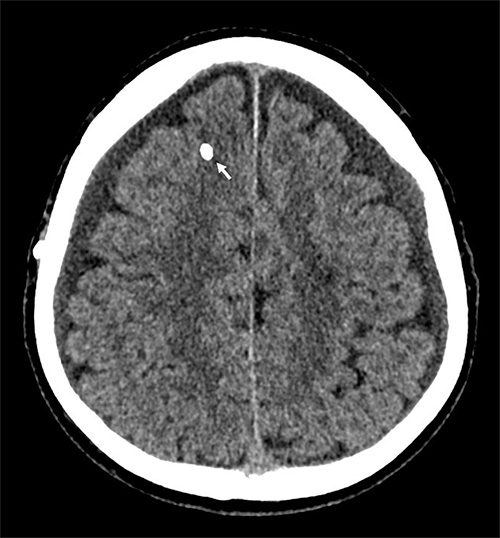

Axial DT-bild av en patient med allvarligt överdränage, vilket har givit upphov till ett akut subduralhematom på vänster sida och ett mindre kroniskt subduralhematom på höger sida. En del av shuntventilen syns subgalealt på höger sida (pil), likaså en del av den röntgentäta intrakraniella katetern.